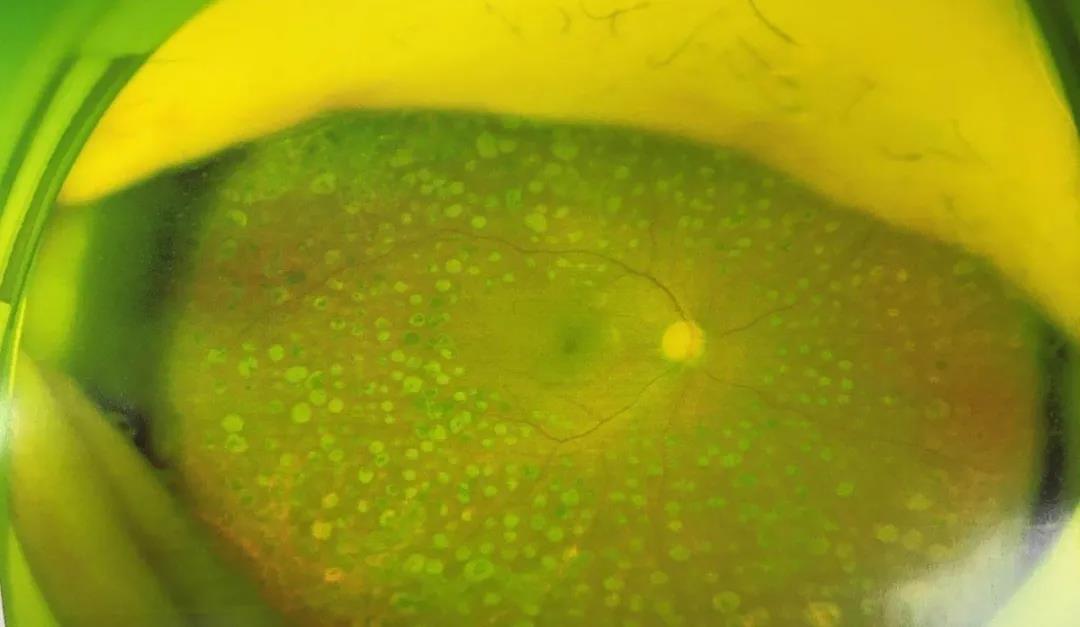

术后眼底对比▼